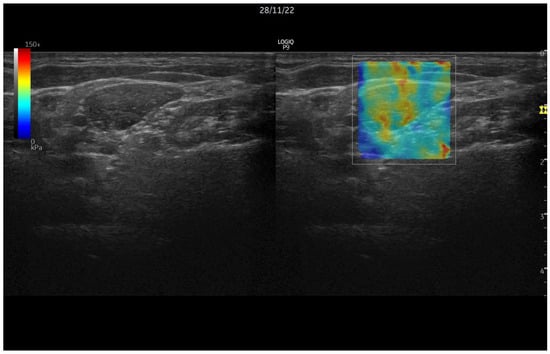

1.2. Ultrasound Elastography